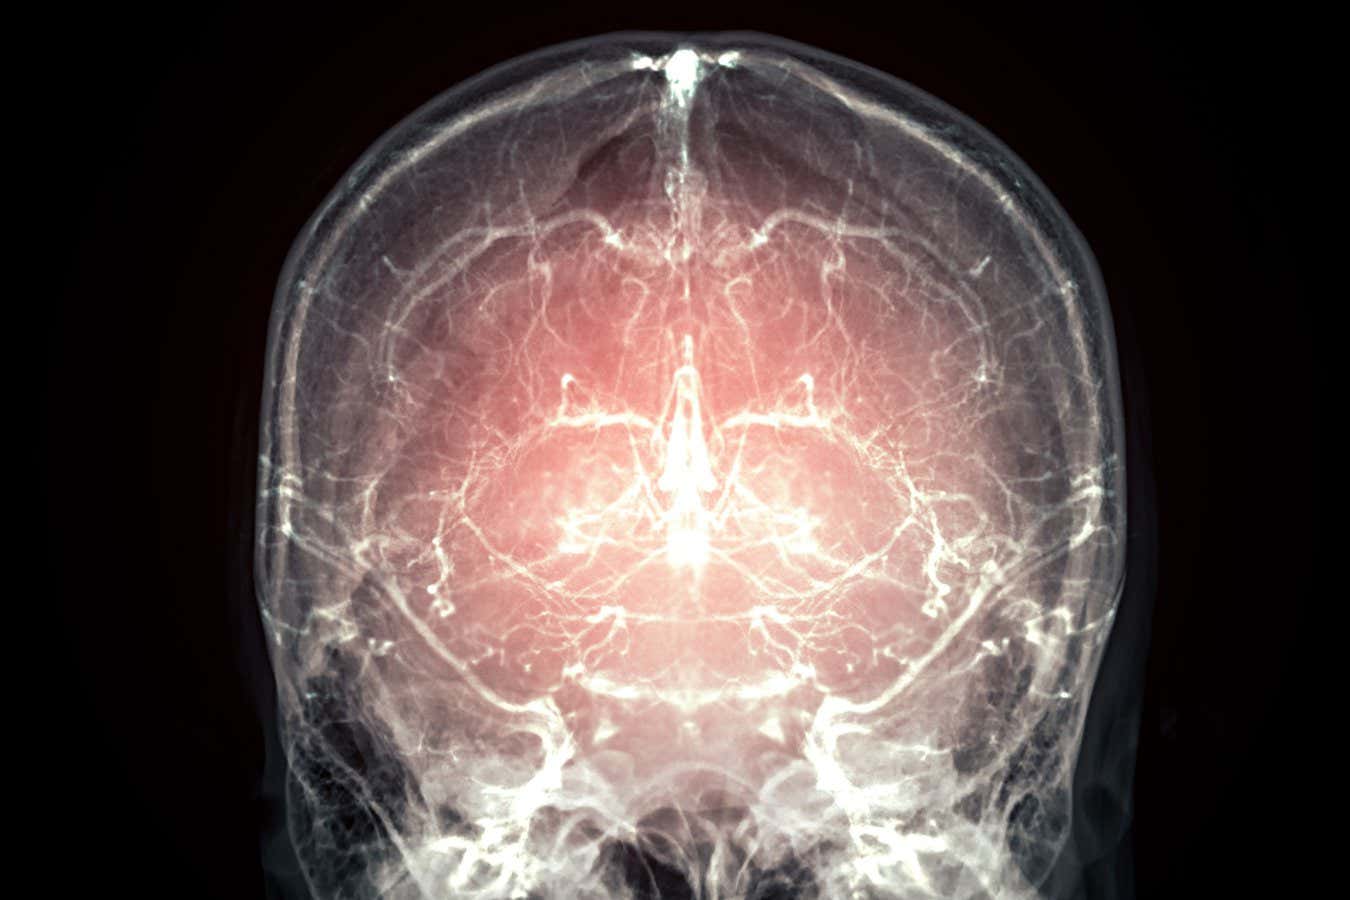

Μια εταιρεία στο Σαν Φρανσίσκο κατάφερε να διατηρήσει έναν ολόκληρο εγκέφαλο θηλαστικού με ελάχιστη κυτταρική φθορά, χρησιμοποιώντας συνδυασμό χημικής σταθεροποίησης και κρυοπροστατευτικών ουσιών. Το επόμενο βήμα; Να προσφέρουν το ίδιο πρωτόκολλο σε ανθρώπους με τελικό στάδιο ασθένειας, με την ελπίδα ότι κάποτε θα είναι δυνατή η ανασύσταση του νου τους.

Η ομάδα του Borys Wróbel κατάφερε να διατηρήσει έναν ολόκληρο εγκέφαλο χοίρου σε κατάσταση που προσεγγίζει εκείνη ενός ζωντανού οργανισμού. Η επιλογή του χοίρου δεν είναι τυχαία: η ανατομία του εγκεφάλου και του καρδιαγγειακού του συστήματος είναι συγκρίσιμη με εκείνη του ανθρώπου, κάτι που κάνει τα αποτελέσματα ιδιαίτερα σημαντικά.

Τα αποτελέσματα ήταν εντυπωσιακά: όταν η διαδικασία ξεκίνησε λιγότερο από 14 λεπτά μετά τον θάνατο, οι ιστοί έδειξαν άριστη διατήρηση των νευρώνων, των συνάψεων και των μορίων που τα συνθέτουν. Η ομάδα πιστεύει ότι με αυτή τη μέθοδο θα μπορούσε κανείς να ανακατασκευάσει το connectome — τον πλήρη χάρτη των νευρωνικών συνδέσεων του εγκεφάλου — που θεωρείται η δομική βάση της σκέψης, των συναισθημάτων και της προσωπικότητας.